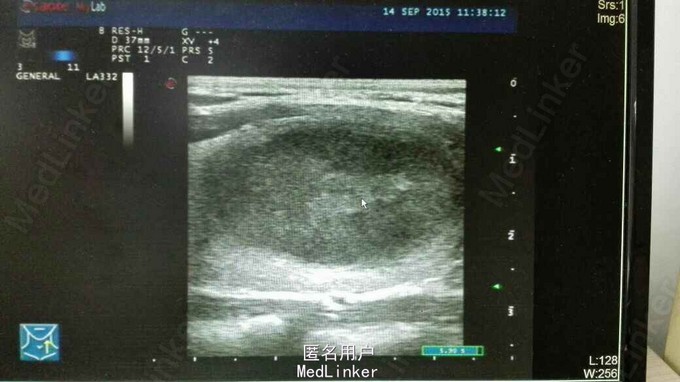

气管居中,左甲状腺Ⅱ度肿大,中下部可扪及一3cm肿物,质中,光滑,边界清,无压痛,可随吞咽上下移动,右侧无肿大,双侧颈部LP(—)。我院甲状腺彩超:甲状腺左侧叶内实性占位病变(33*20*27mm),考虑甲状腺腺瘤可能性大。

1.左侧甲状腺腺瘤,2.肝移植状态。术前充分完善相关检查,排除手术禁忌症后行左侧甲状腺次全切除术,术中冰冻及术后石蜡病理示滤泡性腺瘤形成。